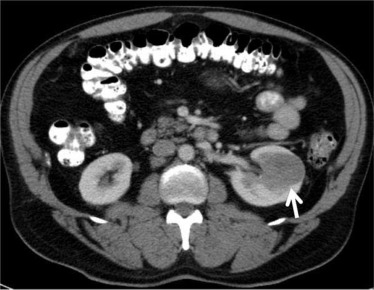

4. Nephrocalcinosis

Calcium deposits may accumulate within kidney tissue, gradually reducing kidney function.

- Imaging: ultrasound or CT scan to check kidney structure